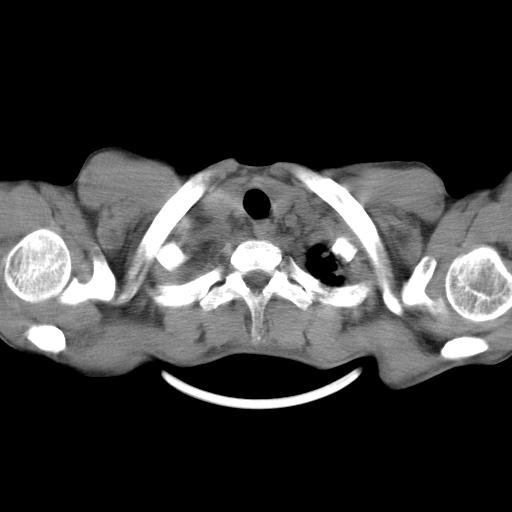

男性,44岁,结核病史多年。现胸闷气短,咳嗽,偶咳血。

双肺多发结节影最分空洞形成考虑占位不除外结核

1、右侧大量胸腔积液伴右肺压缩性膨胀不全,建议抽液治疗后复查 2、两肺继发性tb伴空洞形成。

1)两肺继发性肺结核伴空洞形成,左肺多发性结核球。2)右侧大量胸腔积液伴右肺部分膨胀不全。3)纵隔淋巴结肿大。

吉大一院胸水抽检结果:结核性胸水